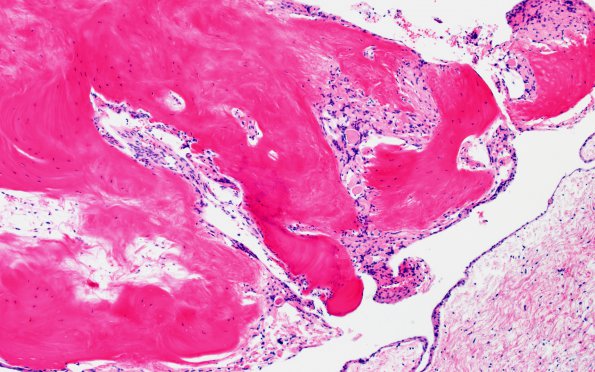

Arachnoid Fibrohyaline Plaques

7A7 (Case 7) Fibrohyalin bone H&E 10X 2

Higher magnification of the lesion shown in image #7A6. (H&E)